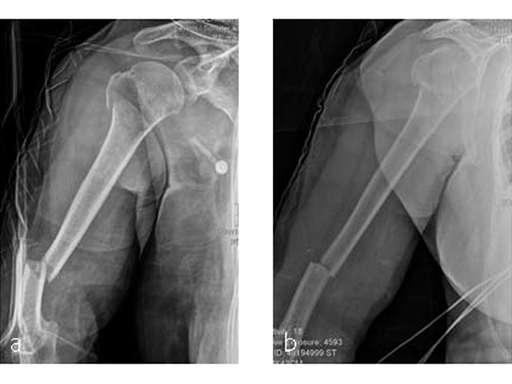

Case 2: Staircase fall (Case provided by Markus Wambacher, Innsbruck, Austria)

Following a fall downstairs, a 70-year-old woman sustained a head injury with intracerebral and subdural haematoma, as well as a complex fracture of the right humerus, representing a minimal displaced proximal and an oblique fracture in the distal part of the humerus (Fig 3).

After neurosurgical intervention, surgery of the humerus was planned 10 days after the index trauma. The patient was still at the neurological intensive care unit and a preoperative clinical examination of the patient, regarding radial nerve palsy, was not possible. Therefore, a surgical revision with exploration of the radial nerve and an osteosythesis of the humerus using a long MultiLoc Humeral Nail was indicated.